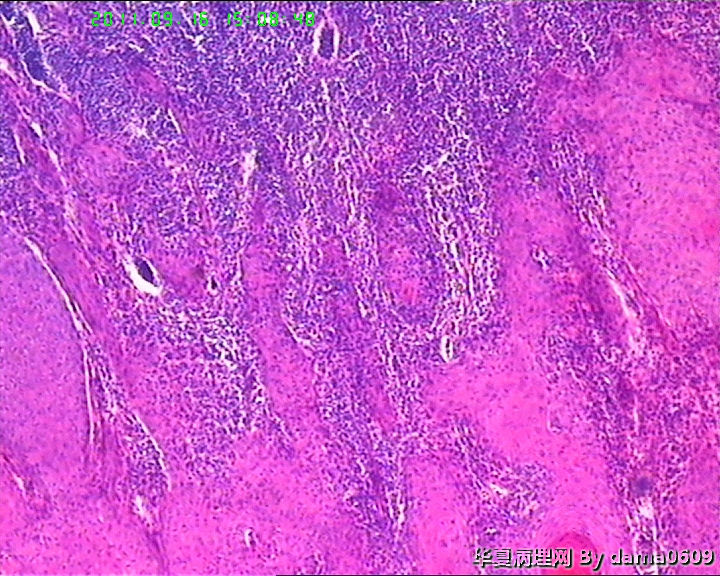

女,背部皮肤肿物,病史不详。送检梭皮组织一块,S:4.5x2.2cm,正中一圆形隆起,直径2.0cm,表面黄白色与周围界清,切面实性灰白色。

• 背部肿物,急请老师看看!!图1

图1